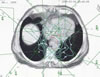

Tumore des Magens